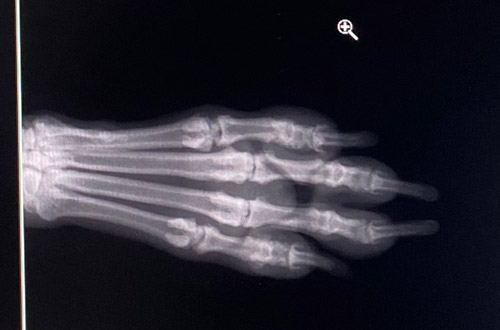

レントゲン結果はと言うと、

指のスジらしき線は、写っていなかったので、くっ付いたと思われる。

爪が伸び、肉球内にあった爪が、外まで伸びて来たので、検査をすると、

やはり折れた形跡があり、そこからの出血だった事が確認ができた。

まだ、折れて再生された場所は、少し軟らかく、ペコペコするらしいけど、

爪の折れは、繋がっているので、とりあえずは、完治って事に。

しばらくは、様子を見ながらにするけど、

復活ができて、ホッとするのでありました。

あすた、完治、おめでとう♪